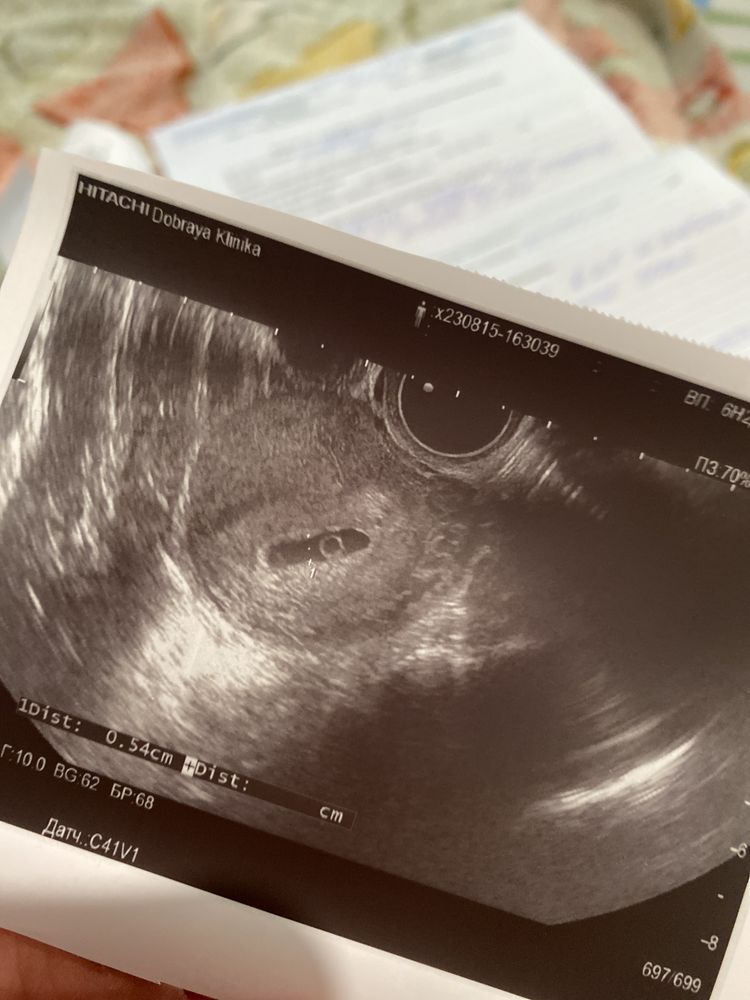

sunvita, К сожалению нервничать меня заставило узи,6н+3 не нашли эмбриона,а в 5 недель была недолгая тянущая боль,я переживала что именно тогда замер плод,на узи пойду только в пн,поэтому для успокоения решила посмотреть хгч в динамике)

sunvita, 6н+3,это было позавчера,в пн пойду к другому врачу

sunvita,Достойных врачей много,всех обзвонила,ближайшая запись в сентябре,буду надеяться малыш подрос и покажется,возможно из-за неправильной формы плодного яйца не заметили